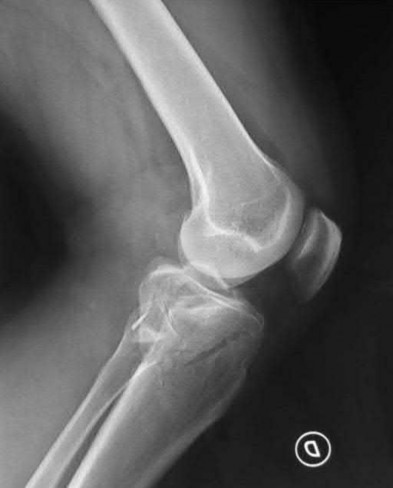

Figure A is an AP radiograph of a posterior knee dislocation. Figure B is a lateral showing the same injury.